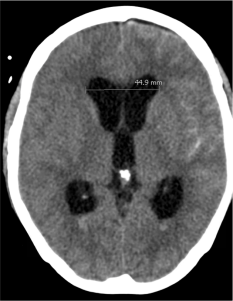

1. Hydrocephalus

Hydrocephalus is the accumulation of the cerebrospinal fluid (CSF) in the fluid-filled spaces of the brain (ventricles). In SAH, hydrocephalus occurs when the blood in the subarachnoid space blocks the normal drainage of the CSF. Hydrocephalus can lead to elevated intracranial pressures (ICPs), which results in decreased consciousness and subsequent coma if not treated immediately. A bedside procedure can be performed where a catheter is placed into the ventricle to drain the CSF. This procedure is called a ventriculostomy or external ventricular drainage (EVD).